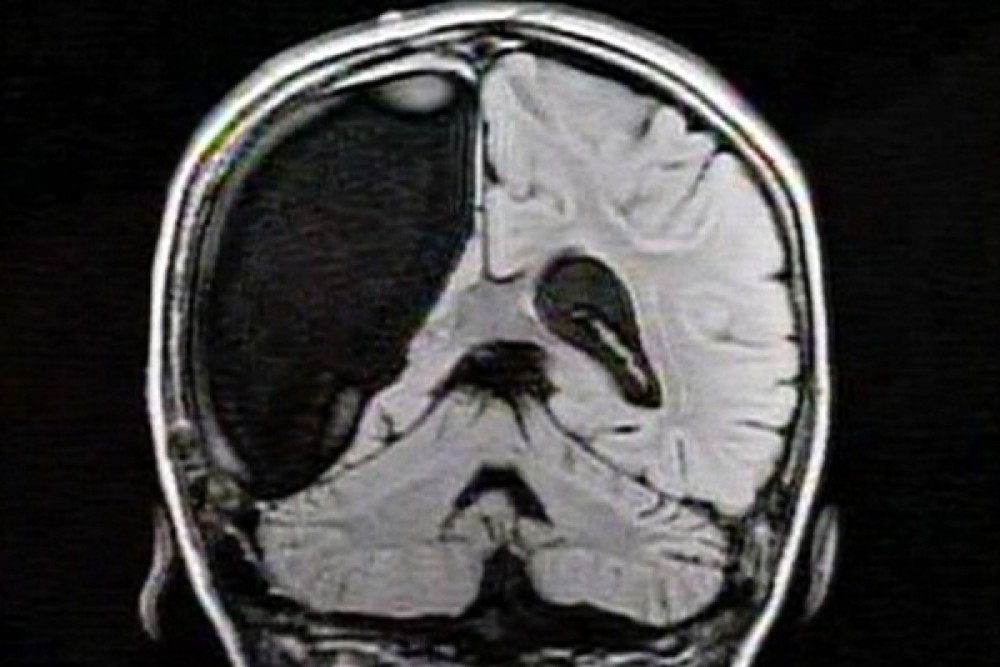

В 2019 году группа исследователей из Калифорнийского технологического института проанализировала мозг шести взрослых людей в возрасте от 20 до 30 лет, перенесших гемисферэктомию — редкую нейрохирургическую операцию по удалению половины головного мозга. Эта процедура показана в экстремальных случаях эпилепсии и проводится аж с конца XIX века. Авторы также проанализировали мозг контрольной группы из шести здоровых людей, у которых были оба полушария. Все участники прошли функциональную магнитно-резонансную томографию.

Результаты показали, что у однополушарных пациентов мозговые сети, которые отвечают за зрение, речь и многие другие функции, были на удивление целы и работают так же, как и у здоровых людей. Более того, авторы обнаружили, что связь между частями различных сетей и их плотность на самом деле выше у тех пациентов, которые перенесли гемисферэктомию. Стало быть, мозг способен не только адаптироваться к условиям, но и компенсировать потерю целостности органа без потери функциональности.